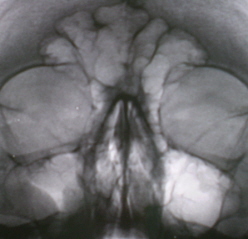

Пример концентрической облитерации представлен на иллюстрациях 11, 12.

На иллюстрации 11 определяется выраженное объёмное уменьшение правой гайморовой полости за счет концентрической облитерации её. Структура пристеночного затемнения в виде довольно широкой полосы, неоднородной структуры, что свидетельствует не о «банальном» отёке слизистой, а о разрастании фиброзной ткани. Слева в гайморовой полости аналогичный процесс – неоднородное снижение прозрачности гайморовой пазухи, с преимущественным разрастанием фиброзной ткани медиально, базально и латерально.

На иллюстрации 12. Справа тотальное снижение прозрачности пазухи за счет разрастания фиброзной ткани, с почти полной облитерацией пазухи. Слева в гайморовой пазухе пристеночное неоднородное снижение прозрачности, неравномерной ширины, с признаками гиперпластического воспалительного процесса.